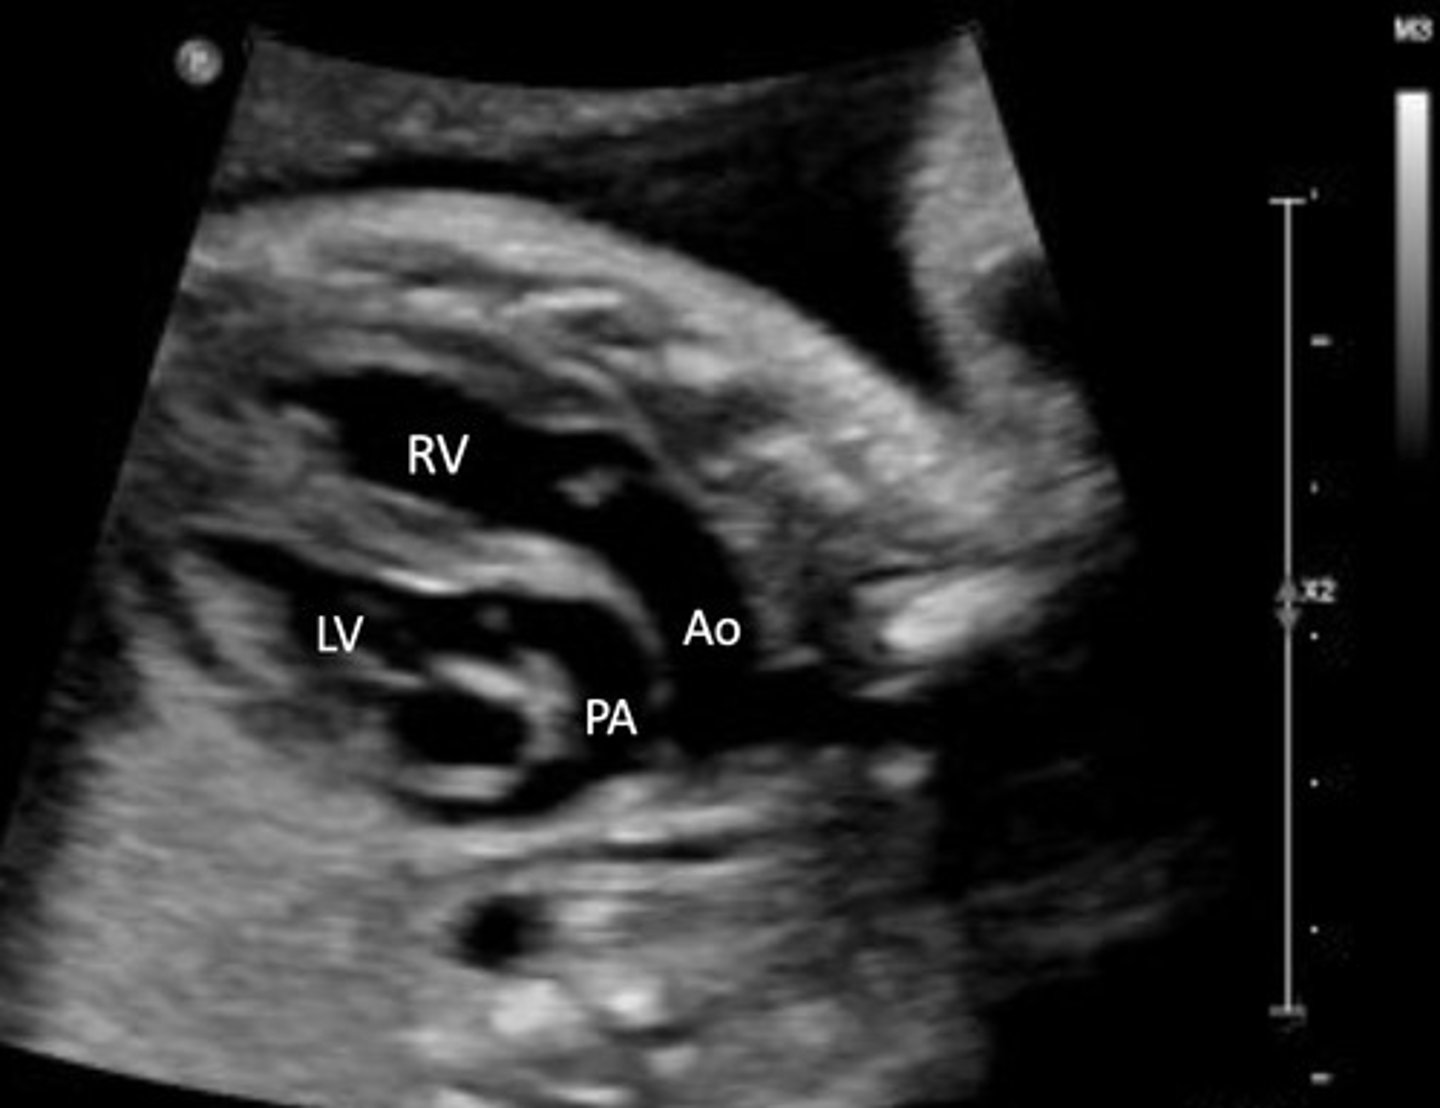

Transposition of Great Vessels

Best seen in PSAX view

Pulmonary A originates from LV

AO originates from RV